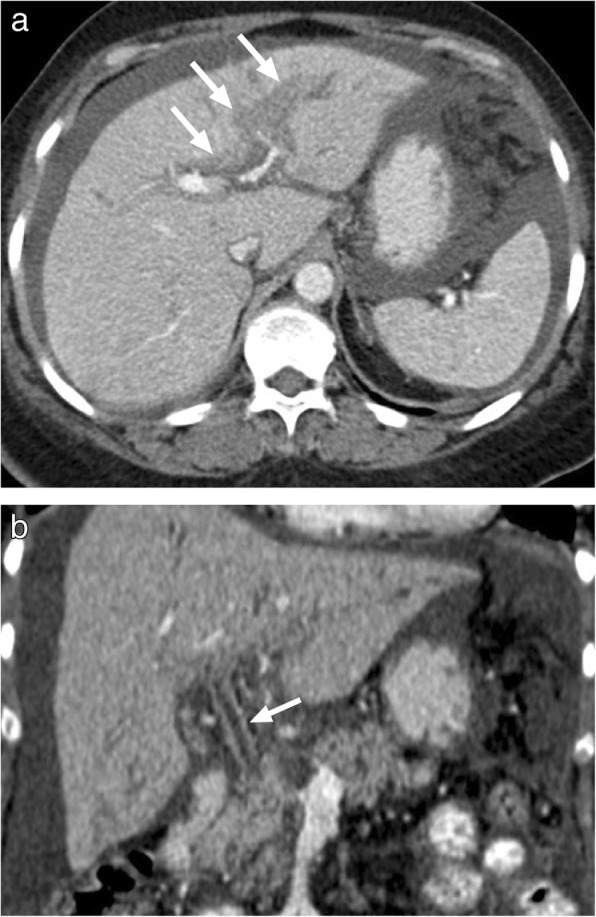

Fig. 25.

A 68-year-old female with known remote history of breast cancer. The patient recently started to experience abdominal pain, distention, night sweets and weight loss. a Axial plane postcontrast CT demonstrated prominent periportal thickening (arrows) in the left liver lobe which may also be seen in infiltrative liver malignancies such as lymphoma. b Coronal reformatted image shows significant contrast enhancement in the common bile duct (arrow). Also note moderate ascites with mild peritoneal contrast enhancement which may also suggest peritoneal carcinomatosis. Intraabdominal fluid sampling and cytology confirmed biliary TB